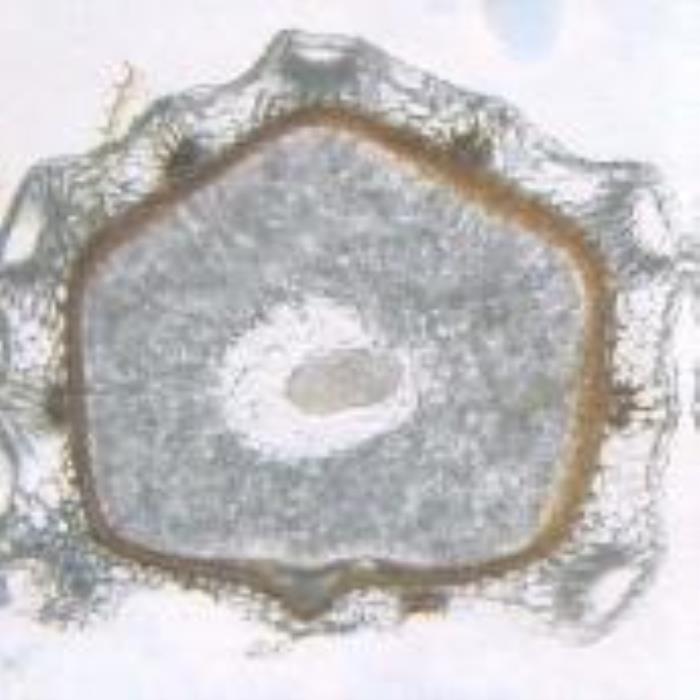

A transverse section of the mericarp is an almost regular pentagon with one of its sides slightly longer which is the commissural surface at which the two mericarps are attached. The epicarp is composed of a layer of indistinct colorless, polygonal, papillose, thin-walled parenchyma covered with faintly striated cuticle. The mesocarp encloses vascular strands on the outer side of which is found a large space (lacuna) just below the epidermis of each primary ridge. Below the epidermal part of the secondary ridges are a group of radiating club-shaped parenchyma cells that are associated with the secretroy canals known as vittae which are filled with dense brown contents. The endocarp is composed of elongated thin-walled cells which are surrounding the seed testa. The testa is composed of one or two layers of thin-walled cells that contain brown pigments. The endosperm of the seed consists of almost rounded parenchyma cells having intercellar spaces. The cells contain aleurone grains and micro rosette crystals of calcium oxalate (DPS, ZCHRTM unpublished results).

(a). TS of the one-seeded khella fruit (mericarp) showing its characteristic features including the pentagon shape brownish seed coat, large endosperm, vascular tissues, vittae, lacunae, and here is showing a cotyledon. (b). Section of the one-seed fruit showing the cotyledons surrounded by the endospermic parenchyma cells. (c). Longitudinal section of the fruit (mericarp) near its tip showing the vascular tissues (dark grey) and the vittae (oil canals, violet brown). (Magnifications: x 100, x 400 and x 100, respectively).